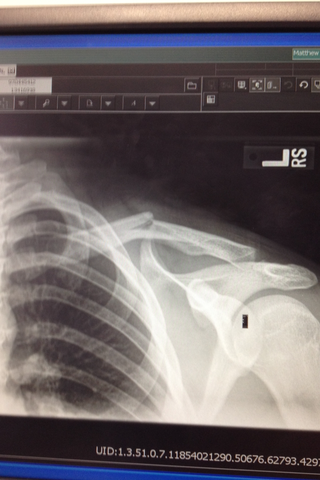

• Broke my Collar bone

Broke my Collar bone

Yo oí el hueso rompí.

Me auydar ellos.

El hueso me dolió.